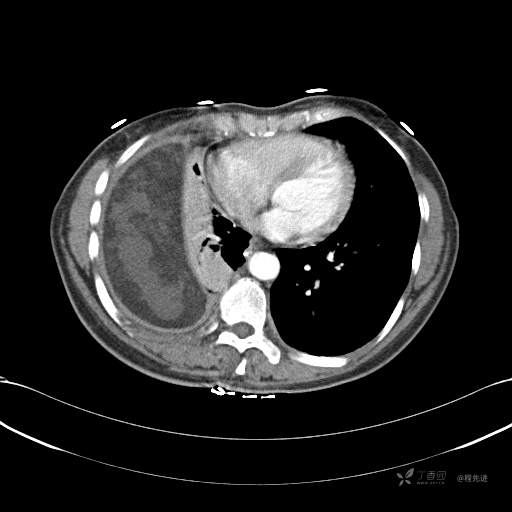

患者性别:女

患者年龄:51岁

简要病史:胸闷半年